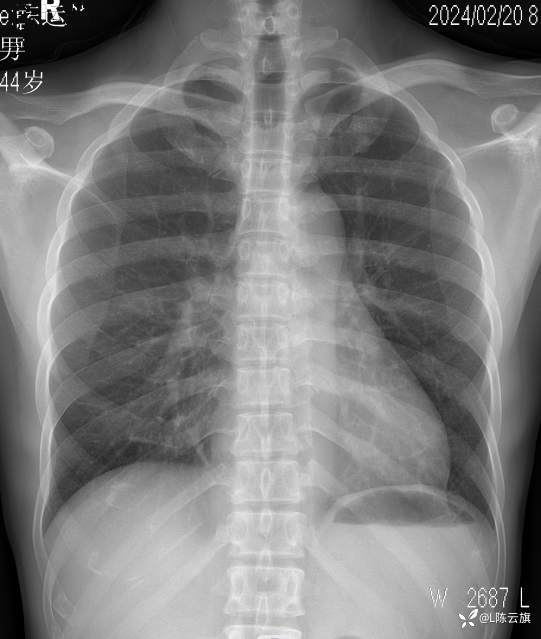

【2403胸部影像病例】 胸部平片你看到的这是什么基本病变?

1、患者男,44岁,精神长期住院患者。近一年反复发热、咳嗽、咳痰,无其他症状。每次进行胸片检查发现肺部炎时,经治疗后病灶吸收,不久又复发。

2、是否可以试述一下病变在哪里?是什么基本病变吗?